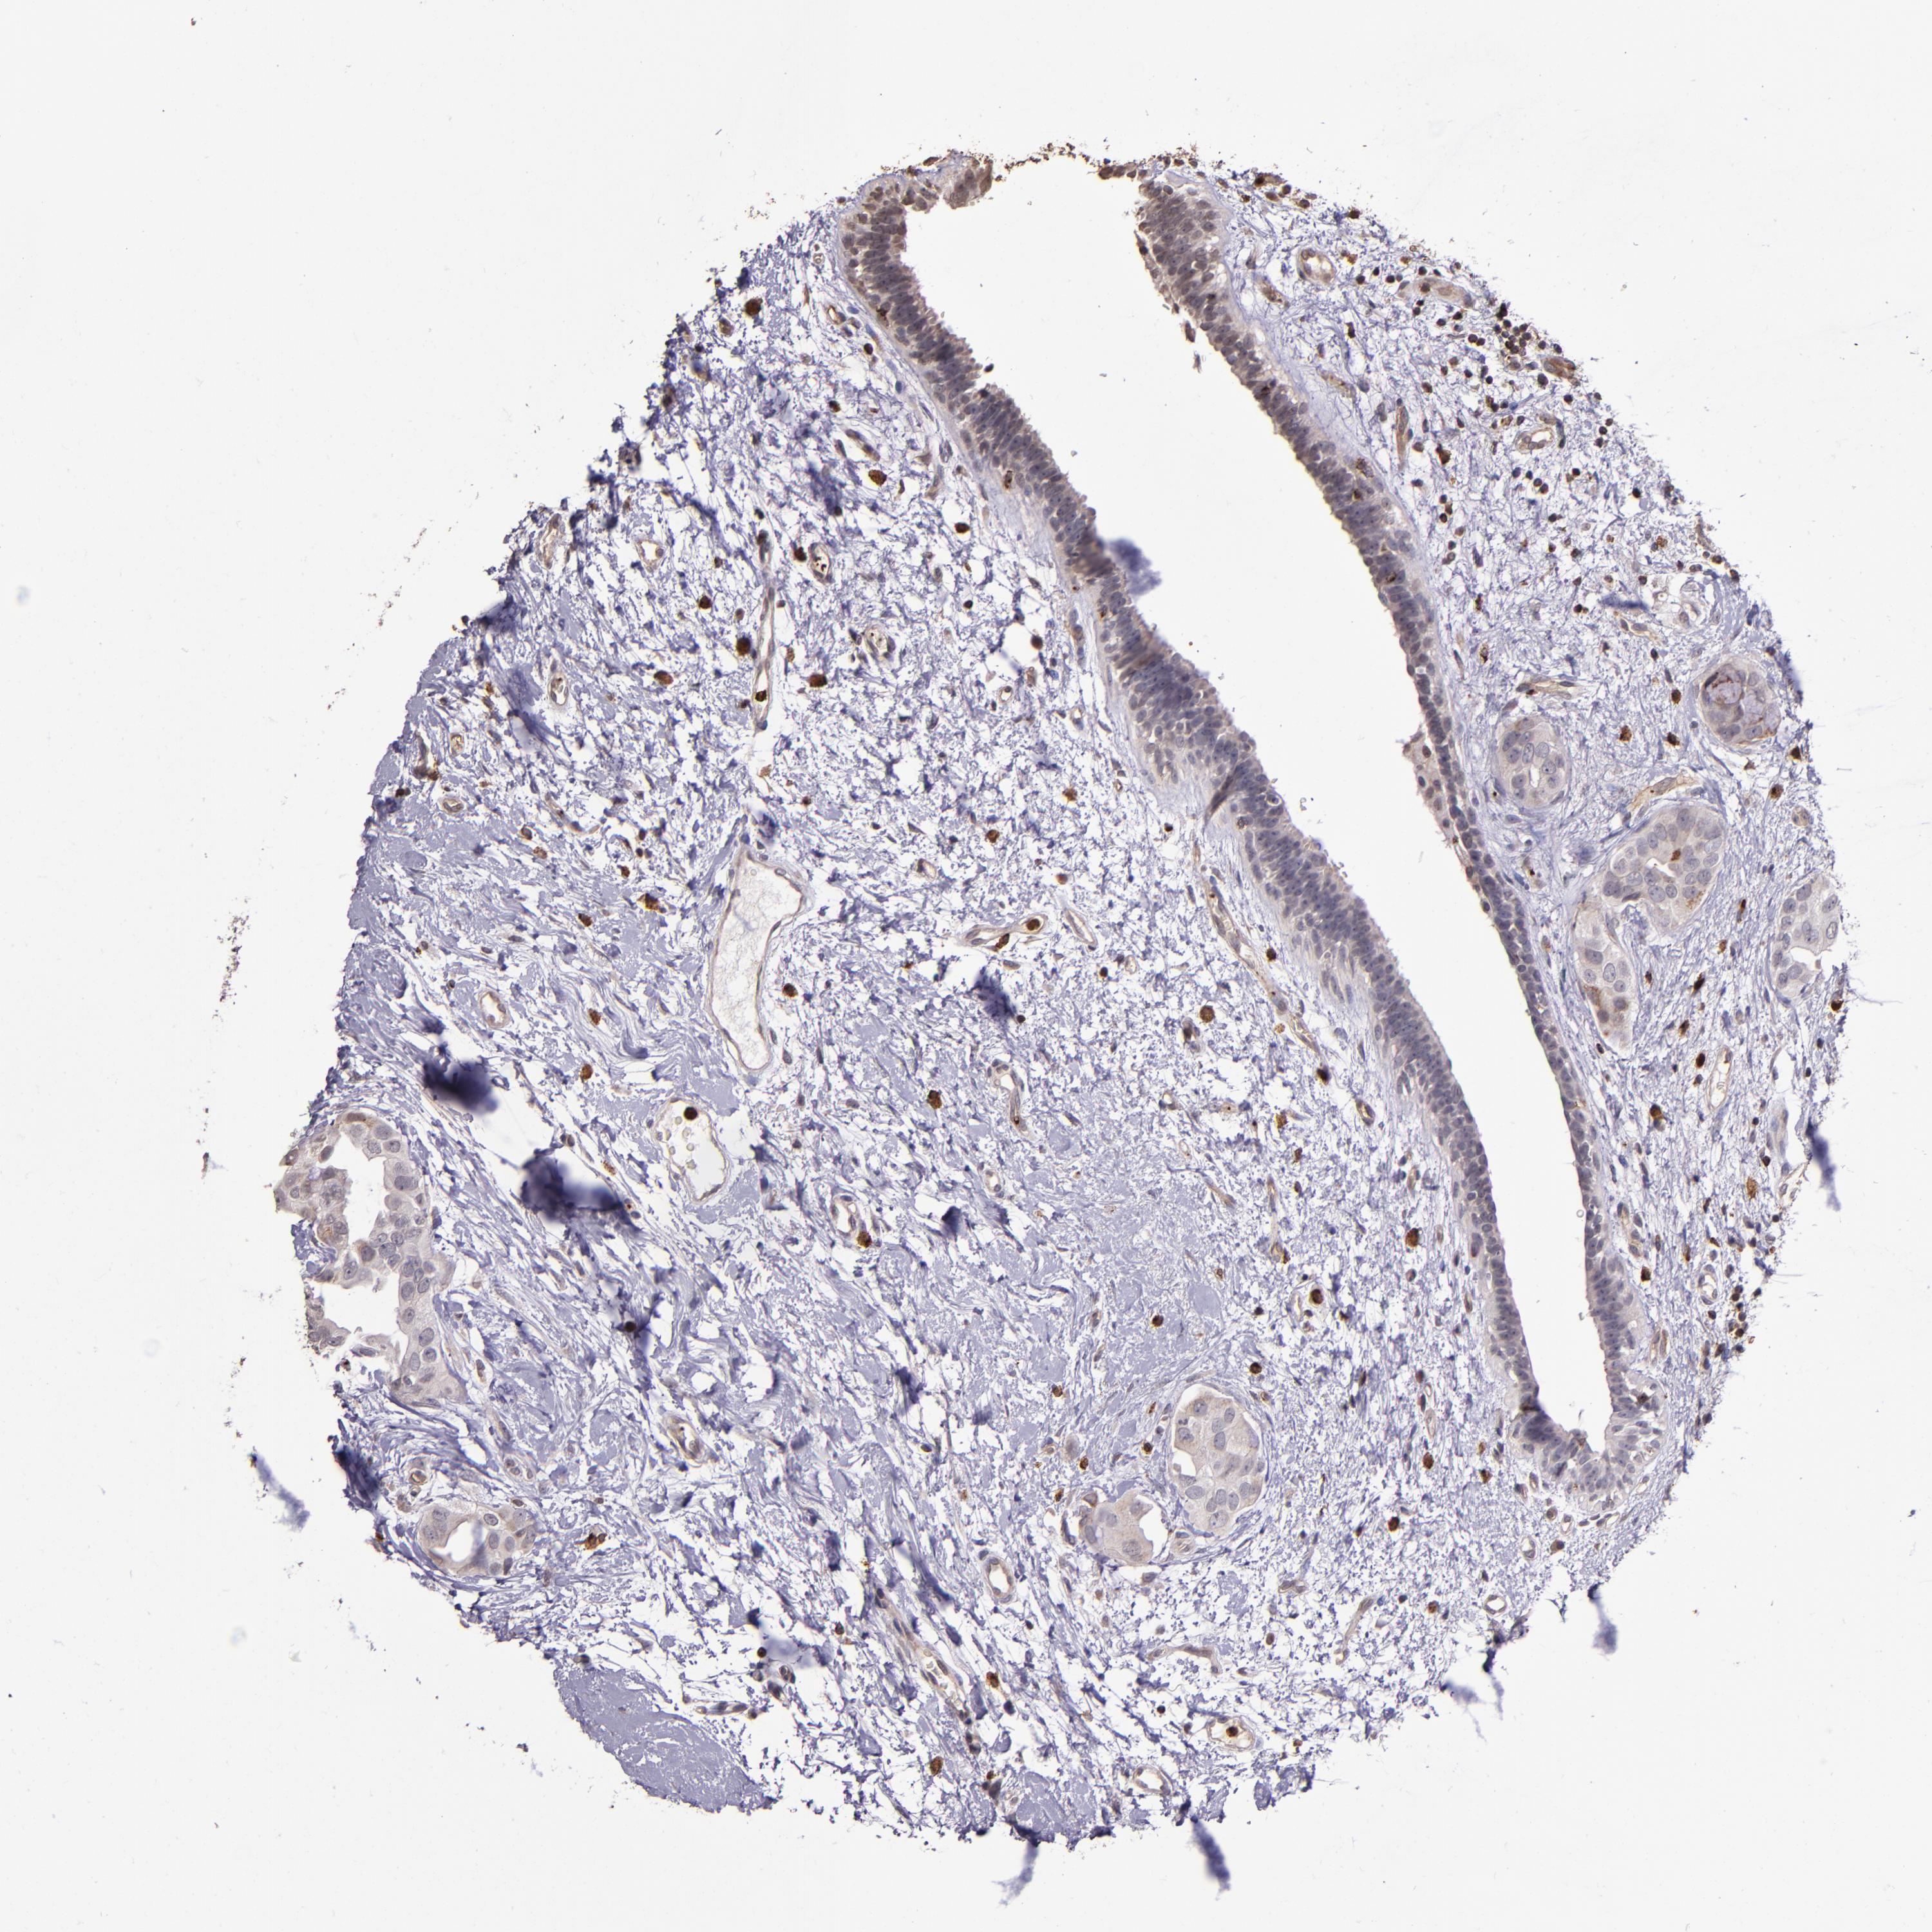

CANCER BREAST CANCER Show tissue menu

BRCA TCGA BRCA VALIDATION PROTEIN EXPRESSION

ANTIBODIES

AND

VALIDATION